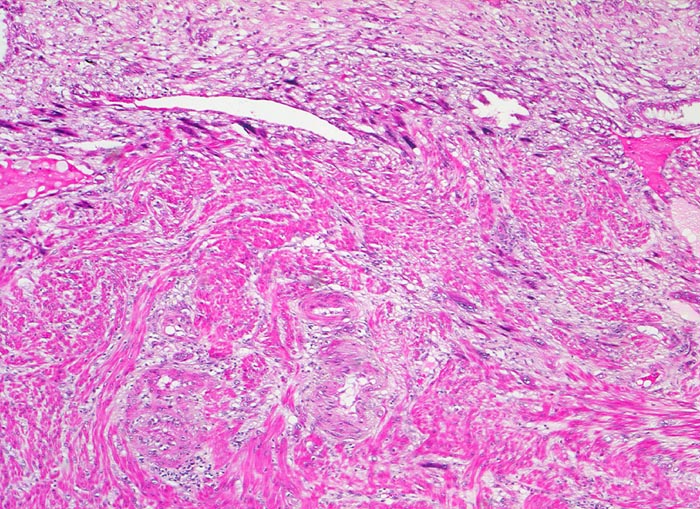

Morphologie:

• Plazenta accreta: Plazentarzotten haften dem Myometrium an ohne deziduale Zwischenschicht. Fibrin und Trophoblast kann vorhanden sein.

• Plazenta increta: Plazentaimplantation innerhalb des Myometriums.

• Plazenta percreta: Penetration der Plazentarzotten durch die gesamte Dicke des Myometriums hindurch.